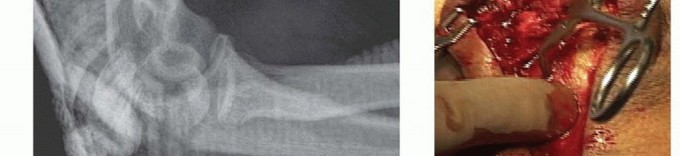

TECH FIG 4 • A. A complex anterior fracture-dislocation of the elbow. A lateral radiograph shows extensive comminution of the trochlear notch of the ulna, including the coronoid, and anterior displacement of the forearm. B,C. The coronoid fragments are connected to the dorsal metaphyseal fragments in this patient, which facilitates reduction and fixation. (A,C: Copyright , MD.)